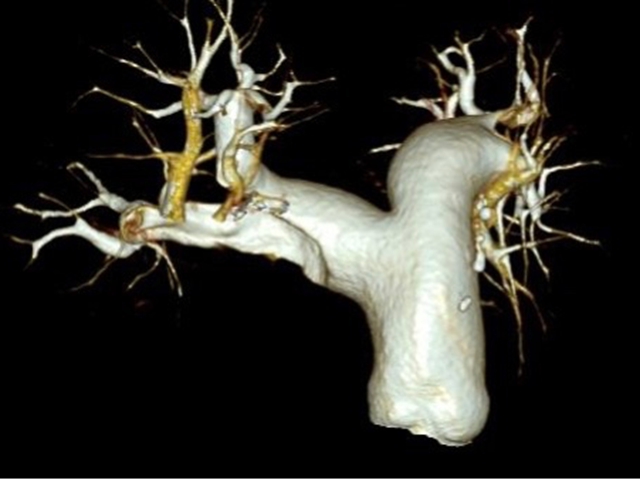

“一站式”CT检查

胸痛三联征“一站式”CT检查是指通过一次扫描、一次注射造影剂可同时显示冠状动脉、肺动脉及主动脉三种血管的图像,有助于早期、快速诊断,同时可以最大程度降低辐射剂量。因此已成为目前评估急性胸痛患者的首选检查方法。

2.主动脉夹层的检测:这一检查能够清楚地显示主动脉的解剖结构,帮助医生观察主动脉夹层并确定其位置和严重程度,及时进行干预。

3.肺栓塞的评估:通过一站式CT检查,医生可以识别肺栓塞并评估其大小以及位置,以指导治疗决策。